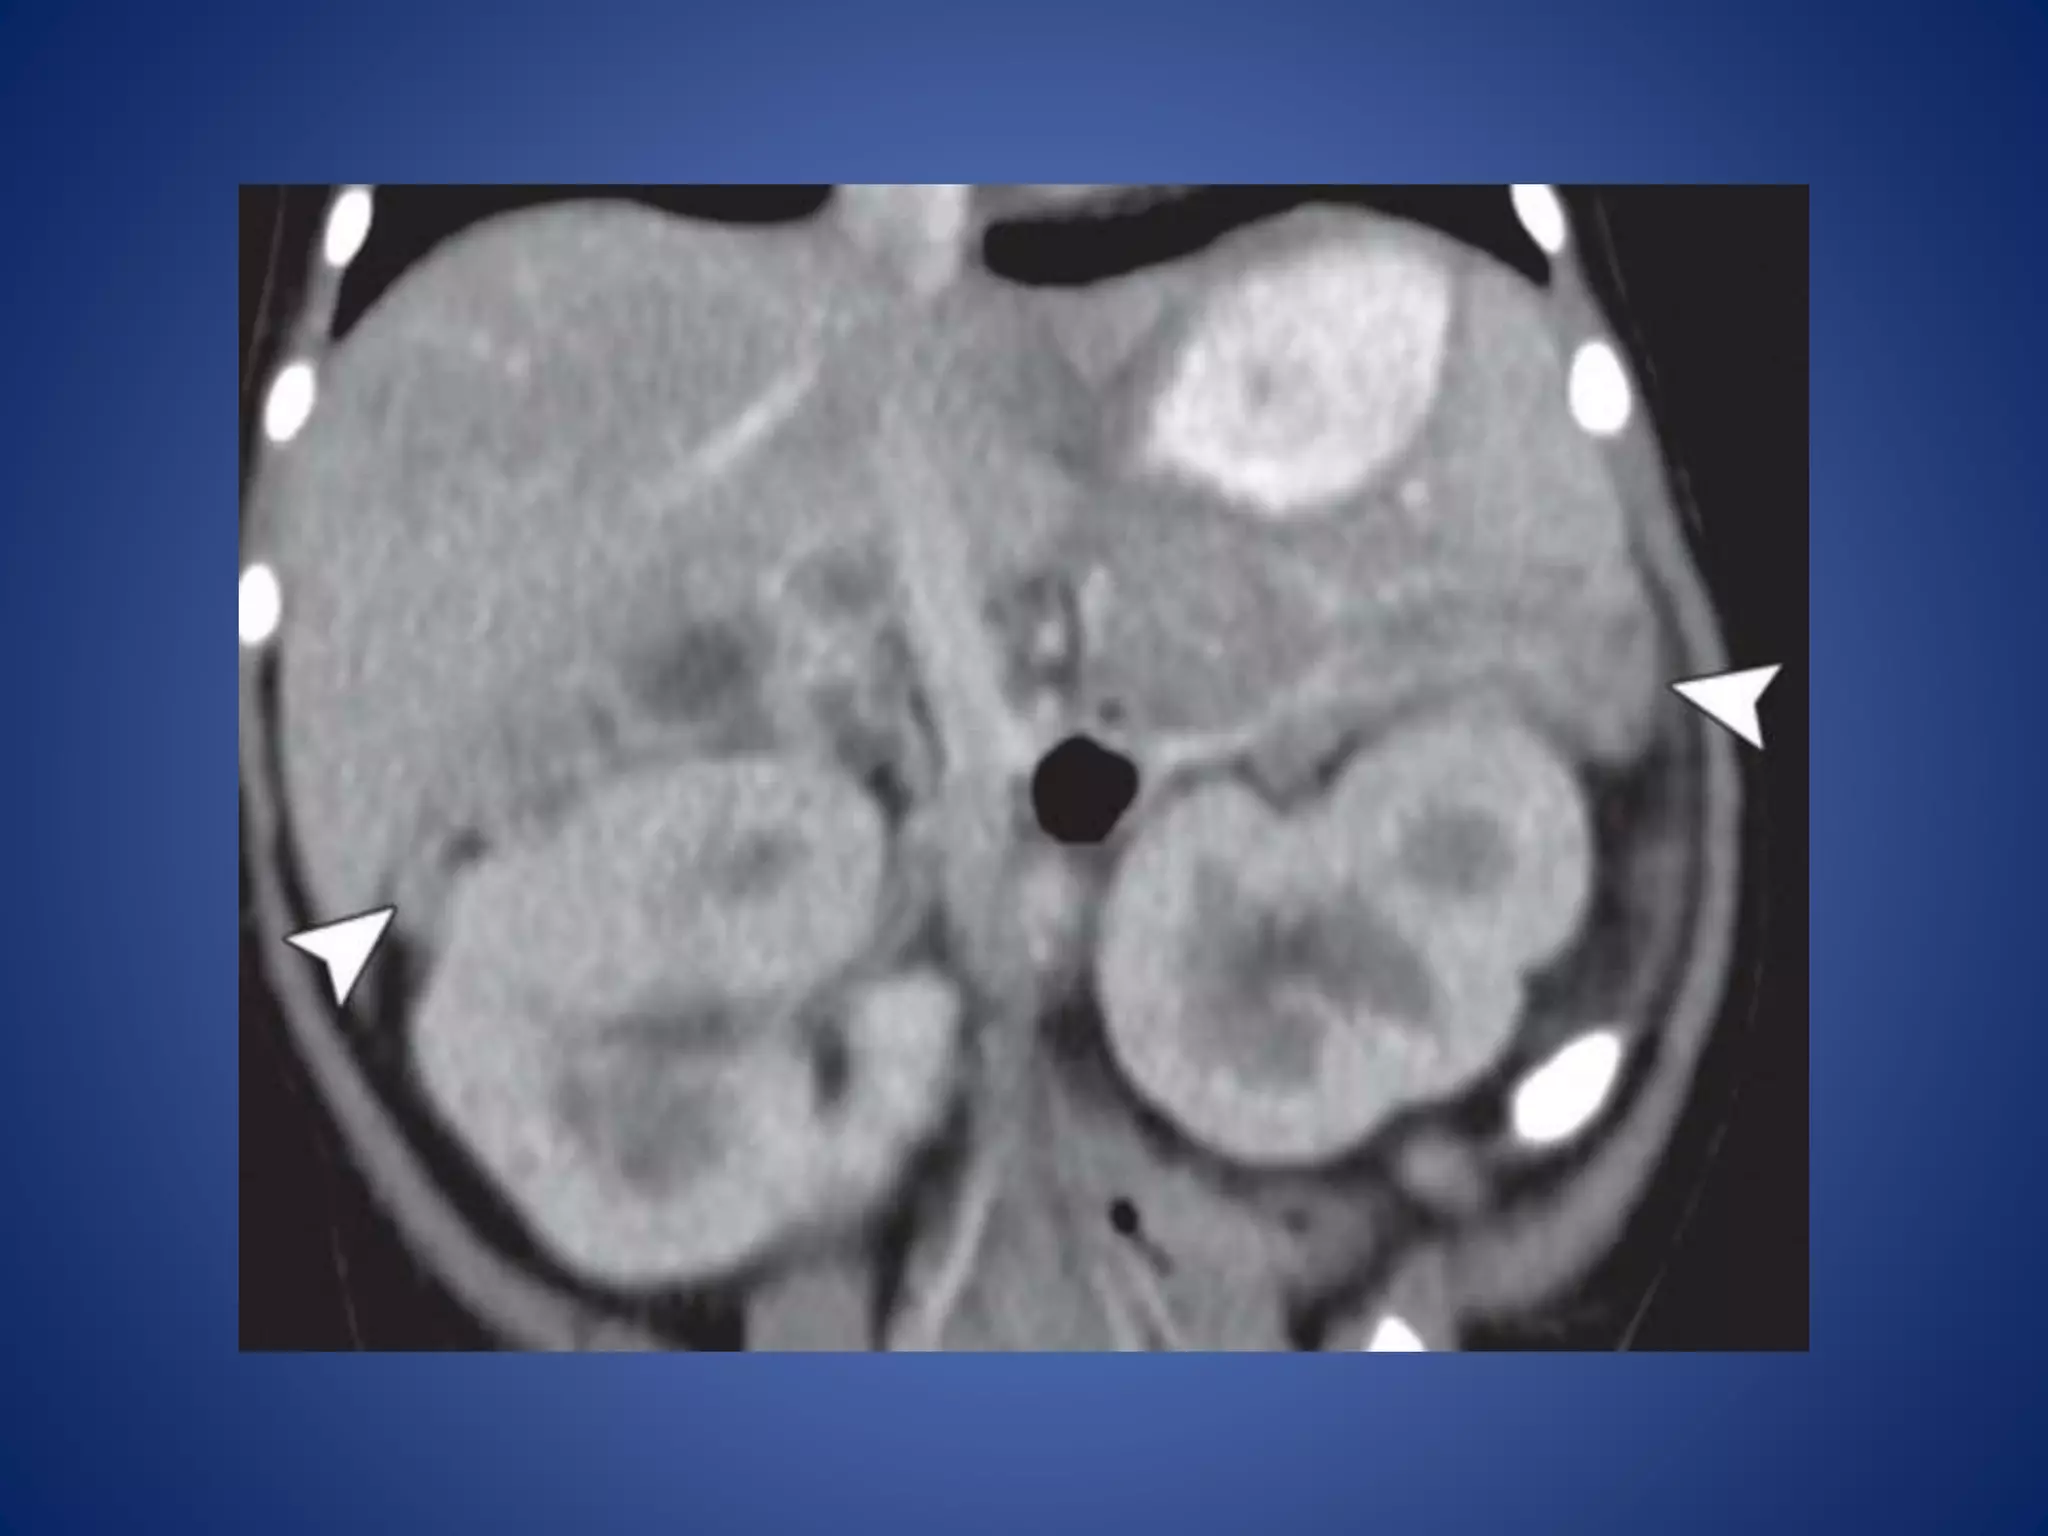

At CT, largeACNs show heterogeneous, predominantly peripheral enhancement. The tumor may be surrounded by a thick, capsule-like rim that enhances. Fine or coarse calcification is seen at CT in about 30% of cases

• #38 ACN in an 18-month-old boy with isosexual precocious puberty and Cushing syndrome. Postcontrast: shows the tumor with an enhancing rim (arrowheads).

• #39 Coronal reformatted CT image shows the left adrenal mass (arrowhead) with enhancing bands in a radiating or stellate arrangement (arrows). Coronal fused positron emission tomographic (PET)/CT image shows increased metabolism in the tumor (arrowhead)